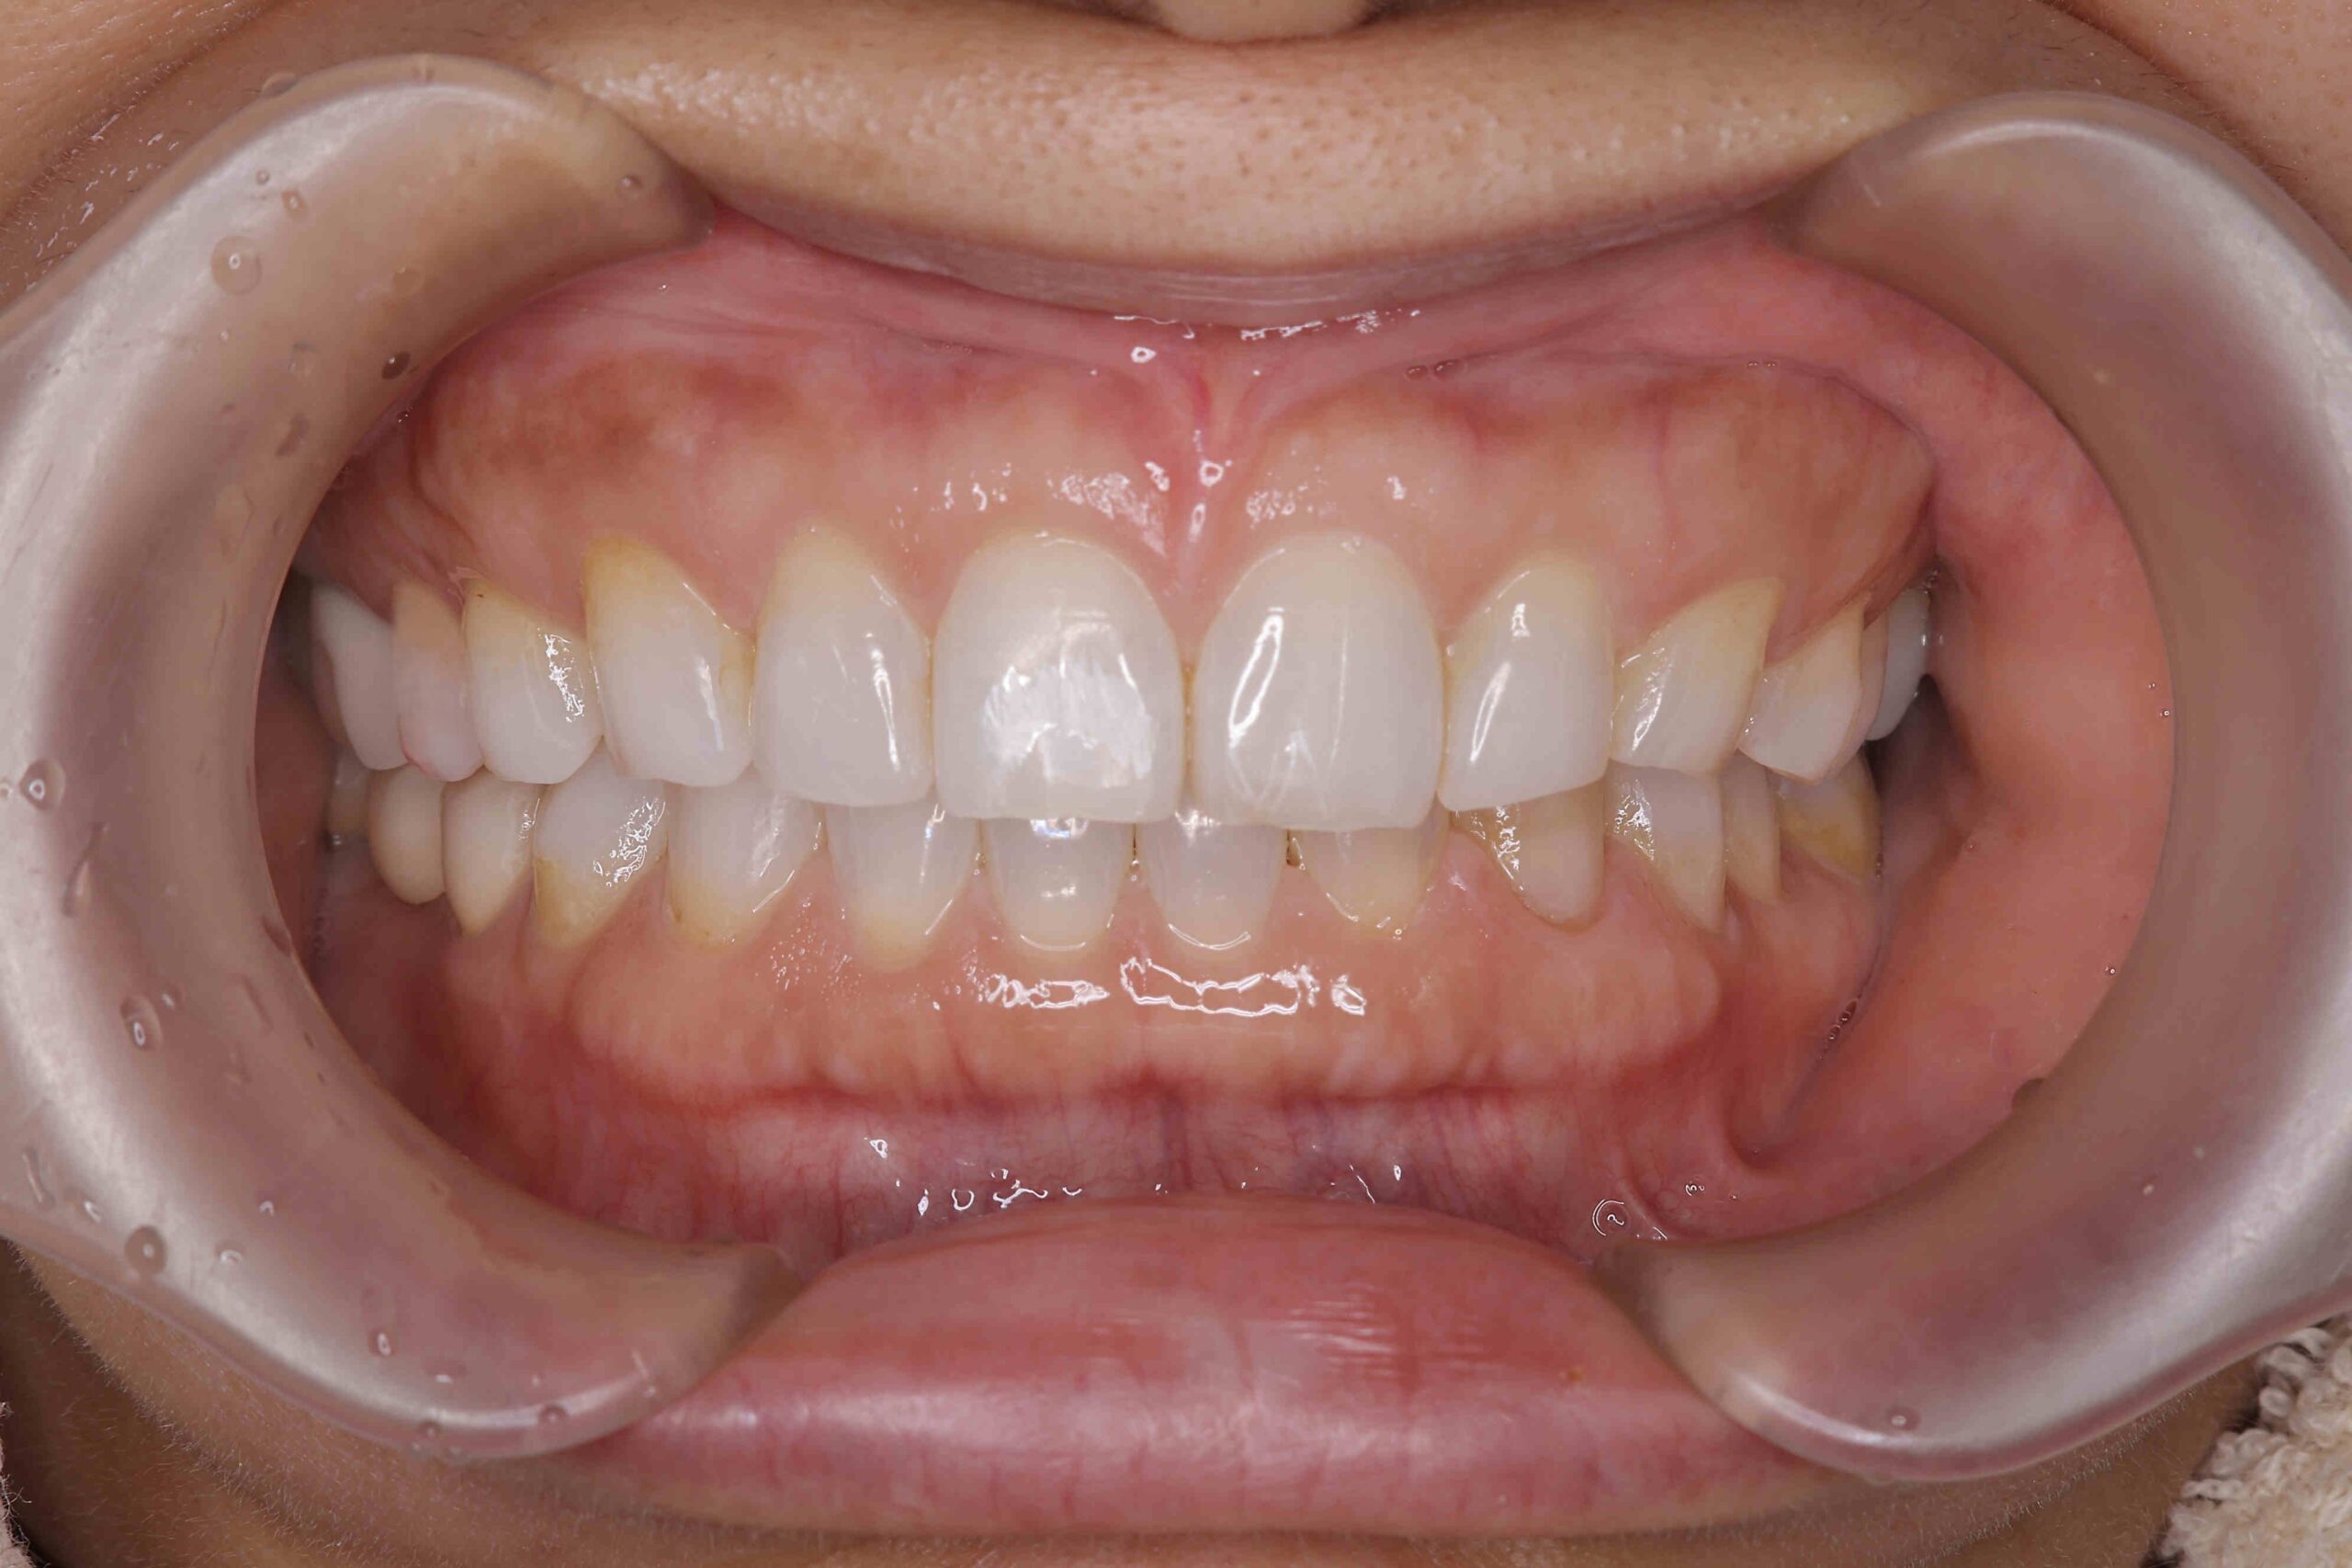

• 治療前

治療後

元々咬む筋力や食いしばり・歯ぎしりが非常に強く、『フレアーアウト』(前歯の歯並びが前方に放射状に倒れていく現象)によって「出っ歯」や「すきっ歯」の状態になっていました。

今回はご希望のマウスピース矯正で、食いしばりや歯ぎしりによる歯の破折やすり減りを予防しながら、歯と歯の隙間が広がって傾斜した前歯を元の位置に戻しました。

ホワイトニングも同時進行で施術し、白く輝く歯になりました。

元々入っていた臼歯のブリッジは治療せず、そのままの位置で矯正を行うことを希望されたため、正中(上顎と下顎の中心線)を合わせることは難しいですが、美しい歯列と口元へ仕上がりました!